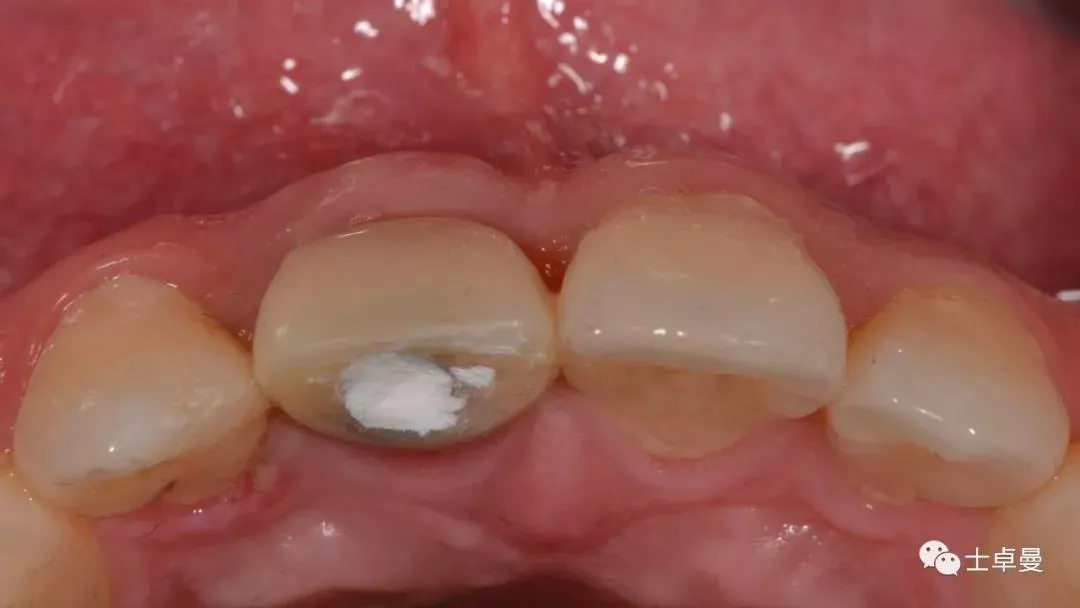

· 主诉:门牙外伤冠折后2月就诊

· 现病史:2月前患者门牙外伤折断,已于我院牙体牙髓科完成根管治疗,但因断冠粘接反复脱落,正畸会诊后示残根牵引将导致冠根比例失调,效果不佳,要求拔除后行种植义齿修复。

口内检查

· 11牙冠折断,余留残根;

· 唇侧位于龈上2mm,腭侧达骨下1mm,根管内封药存;

· 探(-),冷 (无反应),叩 (-),松 (-),牙龈可;

· 中位笑线,牙龈生物型为中弧形、中厚龈生物型;